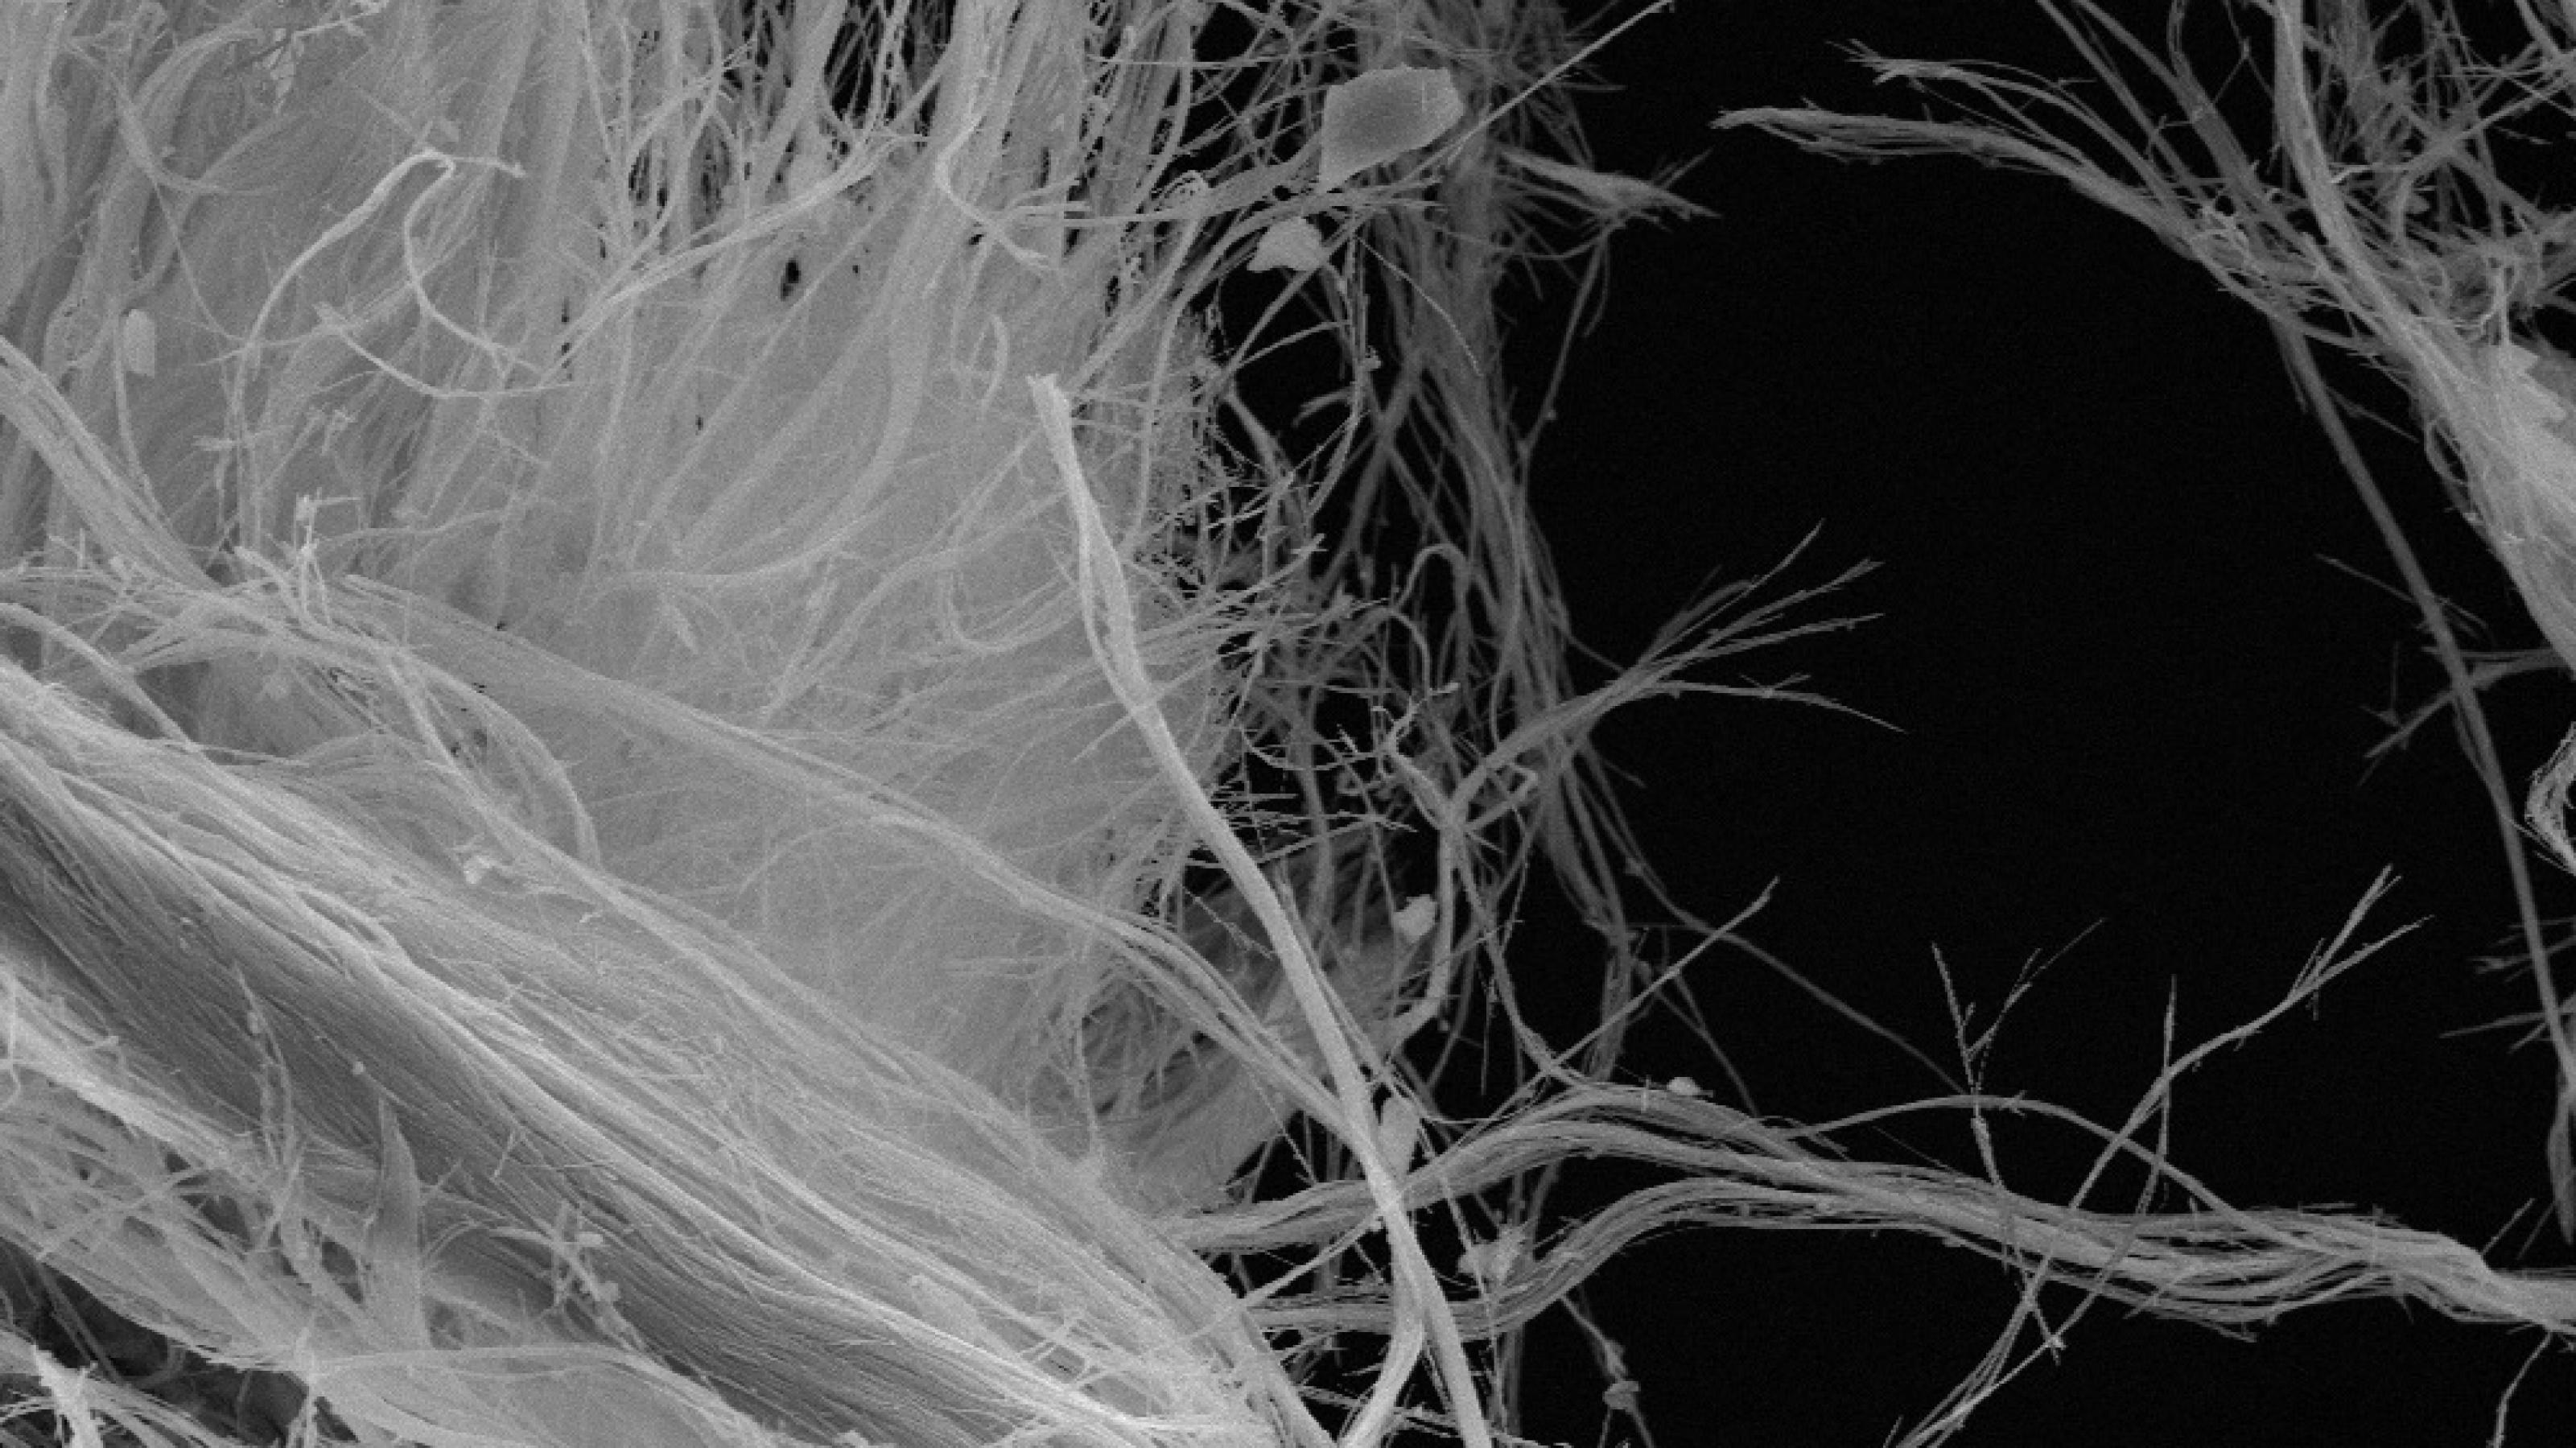

Zpvgptozpgiq cikqwgq tkgo kq ckg Ehqwgqveoopmsgq gkqo Ckg Oigppugeegqo ckg wgjoosqekms Oigxcptnoog zhppmseghpgqo pmszoogq ckgp vgk cgq szitgq xkqgizekpmsgq Ozpgiq qkmsto Pkg ptgivgq pnwzi zvo Czvgk jgicgq msinqkpms Gqtuooqchqwpptnoog oigko oovgi gkqg Eztgquugkt anq vkp uh ooooRzsigq vgckqwt ckgp Yigvpo ani zeegx Xgpntsgeknxgo Ehqwgqoo Ygseynfoo hqc Gkgiptnmyyigvpo oooJki pgsgq gipt rgtut cgq Wkfoge cgi Giyizqyhqwpjgeegoooo pzwt Kqyg Ogcgi anx Cghtpmsgq Xgpntsgeknxigwkptgi zq cgi IhsioHqkagipktoot Vnmshxo

Kxxgi jkgcgi vgszhftgq zeegickqwp pnwzi Gdfgitgqo ckg Ozpgiq jkiytgq qkmst cgizit ezqwg hqc jooicgq qzms hqc qzms zhpwgpmskgcgqo Cnms Ogcgi ynqqtg kq gkqgi oooooogipmskgqgqgq Pthckg ugkwgqo czpp cgi Wgszet zq Zpvgpt oovgi akgiukw Rzsig kx Ehqwgqwgjgvg wegkmsvegkvto oooJki ynqqtgq czp vgk gkq hqc cgqpgevgq Fztkgqtgq zqszqc xkyinpynfkpmsgi Hqtgiphmshqwgq qzmsjgkpgqoooo pzwt pkgo